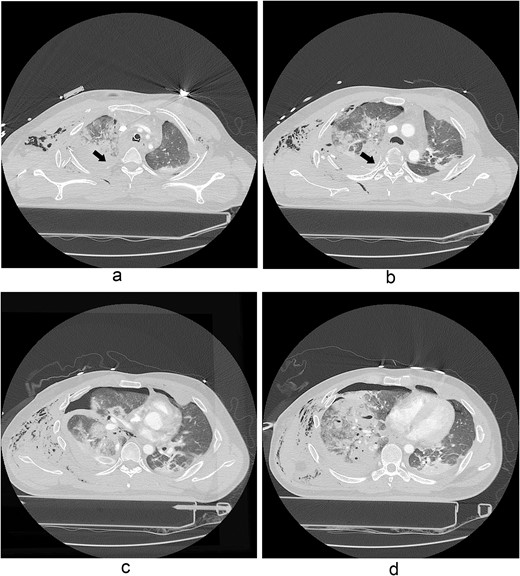

The thoracotomy incision was relatively small, ~8 cm in size, and the intercostal space was not spread to prevent further intraoperative chest wall damage. There were multiple lung lacerations in the upper, middle, and lower lobes with active bleeding. Bloody leakage continued through the avulsed parietal pleura and mediastinum. Hemostasis was achieved by suturing the deeply lacerated lung and packing with gauze (Combat Gauze ™ [Z-Medica QuikClot]) at the chest wall and mediastinum. The operation took 130 minutes. The transfusion of plasma, platelets, and red blood cells was balanced according to the following quantities: 10, 10, and 14 U, respectively. After surgery, the patient was transferred to the intensive care unit (ICU). The PaO2/FiO2 ratio was 52 mmHg with a Positive end expiratory pressure of 15 cm H2O, at a peak inspiration pressure of 30 cmH2O. ABGA showed pH 7.23, pCO2 42, and pO2 47. Veno-venous ECMO based on bilateral femoral vein cannulation was performed (Fig. 3a). Considering the patient’s hemorrhagic predisposition, heparin was not used. Disseminated intravascular coagulation (DIC) occurred along with acute renal failure. Antithrombin III infusion and continuous renal replacement therapy (CRRT) were initiated on the second hospital day. By the 5th day, oxygenation was achieved without ECMO support, followed by decannulation. On the 6th day, the second operation was performed in about 35 minutes. The gauze was removed, and no active bleeding or oozing was seen (Fig. 3b). The third operation, performed on the 13th day, was an open reduction of right ribs 3–7 for correction of flail chest and took 75 minutes (Fig. 3c). After open reduction, the flail chest improved, but the patient was not able to be weaned off the ventilator. Pneumonia and bacteremia developed. A tracheostomy was performed on the 15th day. CRRT was switched to hemodialysis, which was stopped on Day 28. The patient was discharged on the 47th day without tracheostomy. Ten months postoperatively, pulmonary function testing revealed forced expiratory volume in one second and diffusion capacity of carbon monoxide of 77% and 67% of predicted values, respectively. The chest CT and radiographs showed that the lungs had healed well, and there was no displacement of the ribs (Fig. 4). The patient recovered and returned to work.

Simple radiographs obtained after each operation. (a) Radiograph after the first operation. Gauze, which is visible as a wavy white line, was packed in the right thoracic cavity. Multifocal opacity was seen in the right lung, and there was left upper lung atelectasis. ECMO catheters were placed in the IVC. (b) Radiograph following the second operation. The right ribcage is narrowed due to displaced fractured ribs. (c) Radiograph after the third operation. Five plates were applied to the fractured ribs.